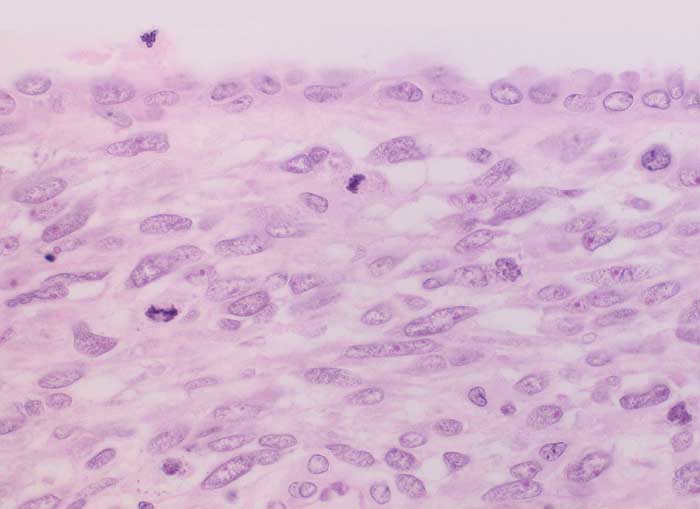

PathoPic ID 6289 - Adenosarkom

Adenosarkom

maligner Tumor

Uterus

Genitalorgane, weiblich

Von gutartigem

Epithel ausgekleidete Zyste. Das angrenzende Stroma ist verdichtet (Kambiumschicht), weist ausgeprägte Atypien und mehrere Mitosen auf.

Postmenopausale Blutungsstörung, sonographisch suspekter Endometriumbefund, klinisch V.a. Endometriumkarzinom.

Histologie

400